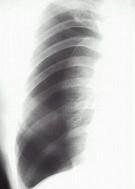

男性,34岁,突感胸部不适,X线检查如图最可能的诊断是 ( )A.肺部炎症B.胸腔积液C.肺结核D.正常心、肺、膈E.气胸

问题 男性,34岁,突感胸部不适,X线检查如图最可能的诊断是 ( )

选项 A.肺部炎症 B.胸腔积液 C.肺结核 D.正常心、肺、膈 E.气胸

答案 E